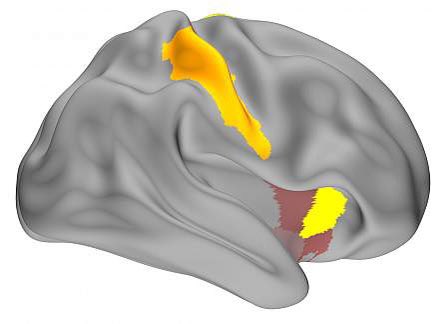

خلال فترة التوقف اتضح ان الأعصاب في المخ تقوم بتكرار نغمة البيانو اكثر من ٢٠ مره.

خلال فترة التوقف اتضح ان الأعصاب في المخ تقوم بتكرار نغمة البيانو اكثر من ٢٠ مره.